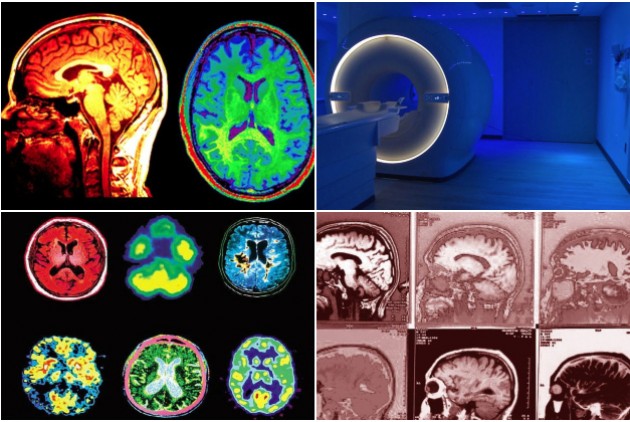

Ετσι, τη δεκαετία του 1980, θα κάνει την εμφάνισή της η Μαγνητική Τομογραφία (MRI), μια πραγματικά μη επεμβατική τεχνική απεικόνισης των εγκεφαλικών δομών που διαθέτοντας μεγαλύτερη διακριτική ικανότητα από την αξονική τομογραφία μπορεί να αποκαλύπτει πιστότερα τις μικροδομές του εγκεφάλου, συμβάλλοντας αποφασιστικά στην ανατομική χαρτογράφησή τους.

Οι εικόνες του εγκεφάλου προκύπτουν από τη δημιουργία ενός ισχυρού μαγνητικού πεδίου που δημιουργείται από έναν ισχυρό μαγνήτη που βρίσκεται πίσω από τα τοιχώματα του κυλινδρικού σαρωτή (scanner).

Το μαγνητικό πεδίο που δημιουργείται στο εσωτερικό του σαρωτή είναι 30.000 έως 80.000 φορές ισχυρότερο από το μαγνητικό πεδίο της Γης και οι σύντομοι αλλά ιδιαίτερα ισχυροί μαγνητικοί παλμοί που δημιουργούνται στο εσωτερικό του σαρωτή υποχρεώνουν τους πυρήνες των ατόμων που υπάρχουν στον εγκεφαλικό ιστό να συντονιστούν, δηλαδή να ευθυγραμμιστούν, πρόσκαιρα, με το ισχυρό μαγνητικό πεδίο, με αποτέλεσμα να αλλάζει η συχνότητα περιστροφής των πυρήνων αυτών των ατόμων.

Μόλις σταματά ο ισχυρός μαγνητικός παλμός, οι πυρήνες των ατόμων επιστρέφουν στην αρχική τους συχνότητα περιστροφής εκπέμποντας πολύ μικρές ποσότητες ενέργειας, υπό τη μορφή μαγνητικών σημάτων, τα οποία καταγράφονται από τους ειδικούς ανιχνευτές του σαρωτή.

Και επειδή η επαναφορά των ατόμων στην αρχική τους κατάσταση γίνεται με διαφορετικές ταχύτητες, δημιουργούνται διαφορετικά «αποτυπώματα» των ιστών.

Συνήθως, οι συσκευές μαγνητικής τομογραφίας χρησιμοποιούν ανιχνευτές που συντονίζονται μόνο με τα μαγνητικά σήματα που εκπέμπουν οι πυρήνες του υδρογόνου, δηλαδή του βασικού συστατικού του ύδατος.

Συνεπώς, αυτές οι απεικονίσεις βασίζονται στην πυκνότητα και την κατανομή του ύδατος στους εγκεφαλικούς ιστούς.